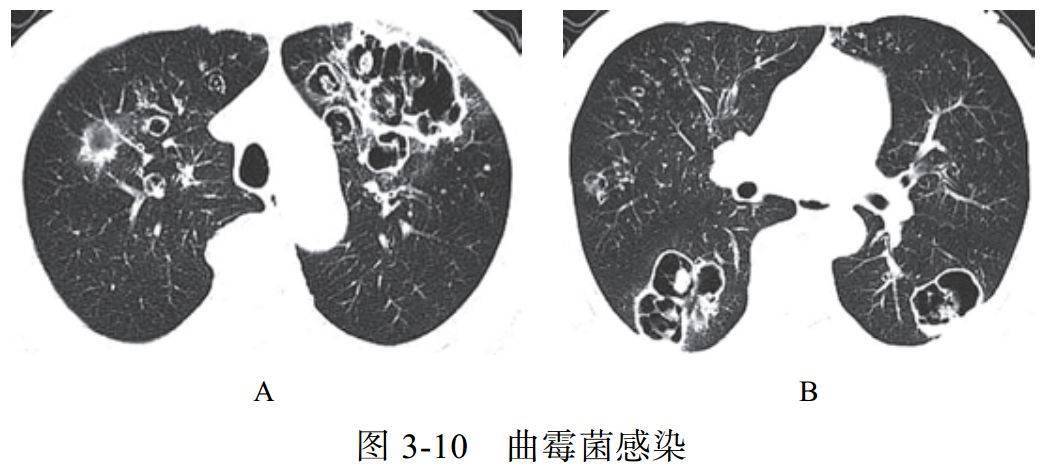

影像学改变:

(1)典型征象为曲菌球(图 3-10)、空气半月征、手套征

(2)多样化病灶并存,可伴有晕征、空洞、洞丝征及树上挂果征

(3)曲菌球随体位改变而变化,球形内容物一般较光滑,密度均匀